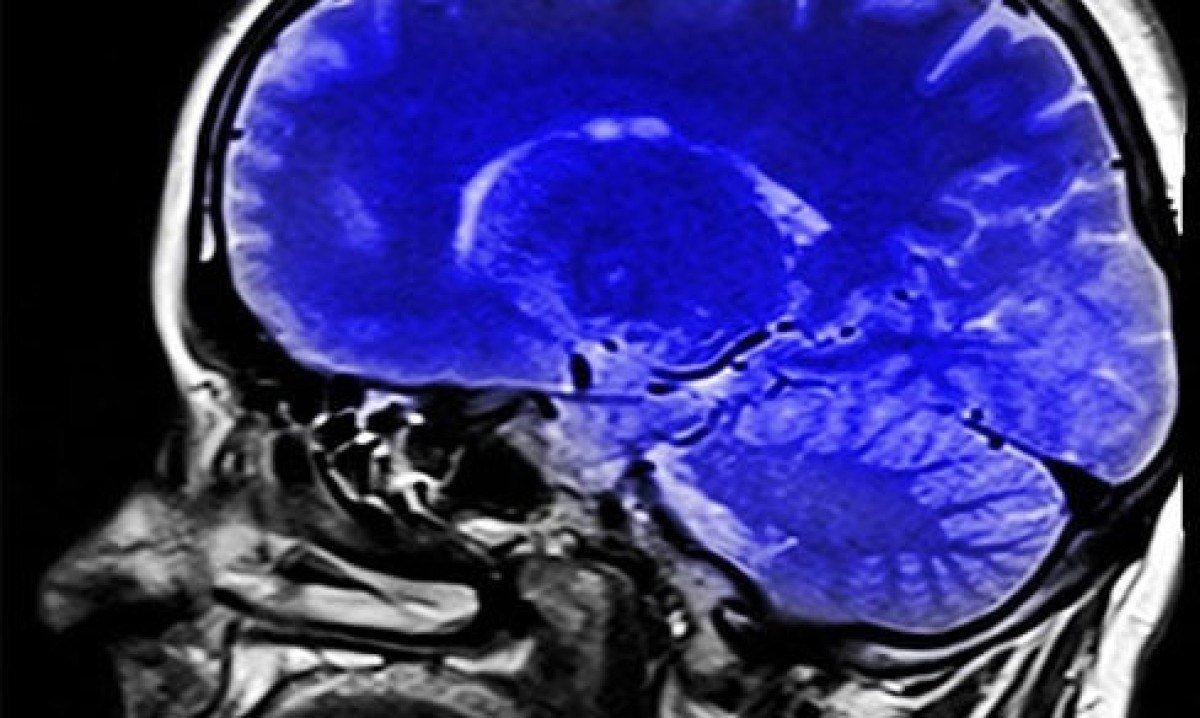

A colina, então, é um nutriente que desempenha um papel crucial no desenvolvimento do cérebro, no funcionamento do sistema nervoso e no metabolismo. Foto: reprodução -

A colina é importante para que o corpo produza acetilcolina (necessária para o desenvolvimento de memória, pensamento e aprendizado), um neurotransmissor que emite as mensagens do cérebro para o corpo através das células nervosas. Foto: Imagem de Alex Dante por Pixabay -